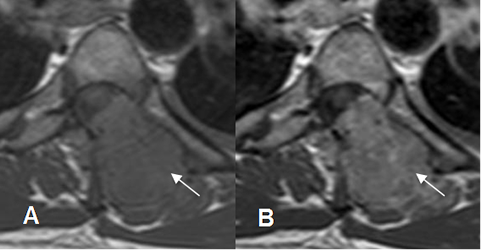

Fig 13. Contraste en RM.

A: RM axial en T1 simple y B: RM axial en T1 con contraste. Lesión metastásica que compromete el sacro, con masa de tejidos blandos. Hay realce heterogéneo del contraste, que indica zona de necrosis central. (Flechas).